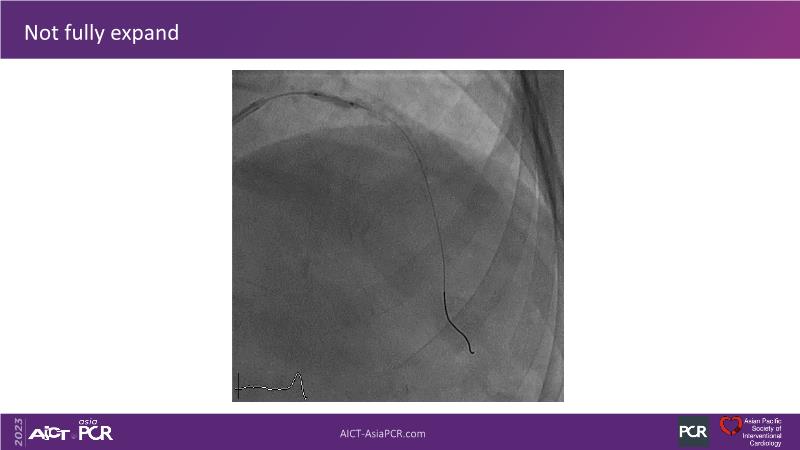

This session is recommended for you if you are seeking insights into the advantages of using IVUS imaging over visual assessment for better outcomes in left main bifurcation procedures. Discuss with experts the benefits of using RotaCUT in lesion preparation for left main bifurcation and explore the impact of high radial strength stents on the procedure's success.

• To see advantages of RotaCUT as part of lesion preparation in left main bifurcation